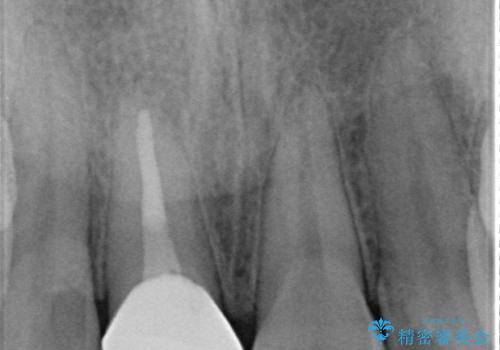

- 他院にて根管治療を行っていたが、痛みが引かないので診て欲しいといらっしゃった方の症例です。

マイクロスコープ下でラバーダムを使用しながら根管治療を行い、痛みが治まった後にオールセラミッククラウンによる補綴を行いました。

- 根管治療により類似の全ての症例の問題が解決するわけではなく、症例はあくまでも一例です

- 根管治療により痛みや腫れがひかない事や、術後に痛みや腫れが生じる事、治療によるファイル破折やパーフォレーションなどの偶発症、術後の歯根破折を生じる可能性もあります